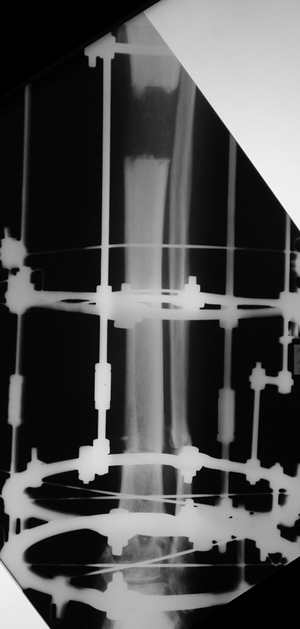

остеотомия м\б кости, аппарат Илизарова. По рентгенограммам в двух проекциях произведено планирование устранения смещений (рис 2 и 3), между вторым и третьим кольцом установлены 6 телескопических дистракторов Гесапода, данные введены в программу, и далее втечение 10 дней больная подкручивала телескопы согласно выданной компьютером инструкции. По завершению репозиции гексаподные телескопы обратно заменены на обычные штанги от аппарата Илизарова (рис 4 и 5). Еще через две недели забит гвоздь (рис 6, контроль

через 4 месяца).

Адаптация отломков гексаподом за 5 дней (рис 5). Замена гексапода на обычные штанги (рис 6 и 7)